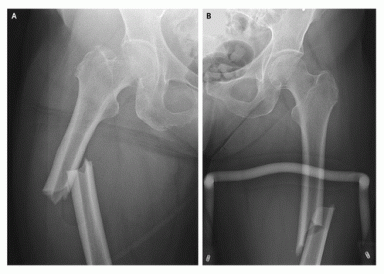

For years, I have been warning patients, friends and family members about the adverse effects of osteoporosis drugs.  Finally, after years of dragging their feet, the FDA issued a news release (Oct 13, 2010) warning of “possible” risk of femur fractures caused by the osteoporosis drugs such as fosamax, boniva, and actonel, etc.  They also added a new warning label  which was recommended by a Task Force assigned to look into this issue.  The Task Force found that almost all women suffering from atypical fractures of the mid femur were on these drugs. Left image: femur fracture while on alendronate courtesy of NEJM.

incidence of femoral shaft fracture in women treated with bisphoshonatesLeft image : Cortical Thickening, and obvious Tranverse Mid Femur Fracture in a patient on osteoporosis drugs-  Bisphosphonate. Image courtesy of Dr Jörg Schilcher and Per Aspenberg, Acta Orthop . 2009 August 7; 80(4): 413–415. Incidence of stress fractures of the femoral shaft in women treated with bisphosphonates.